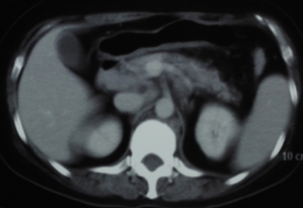

腹部CT:肝胃韧带、肝十二指肠韧带、门腔间隙、胰腺周围、腹主动脉周围多发大小不等的软组织结节影,部分融合成团。

治疗2周期、4周期后肿瘤标志物及CT变化情况如下:

腹膜后淋巴结治疗3月(4周期)